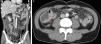

Emergency hemogram showed a left shift with no leukocytosis. With the suspicion of an eventual post-endoscopic complication, an abdominal CT scan was done that identified pneumoperitoneum, free fluid, and thickening of the terminal ileum and Bauhin's valve (a finding in concordance with the endoscopy) (figs. 2a and 2b). Emergency surgery was performed that revealed peritonitis secondary to a punctiform perforation in the terminal ileum 5cm from the ileocecal valve associated with the presence of multiple small ulcerous lesions and a stricturing cecal lesion. Right colectomy with ileocolic anastomosis was performed.